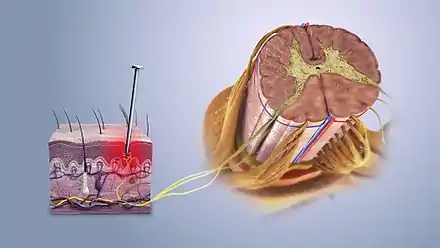

Some sensory fibers do not differentiate between noxious and non-noxious stimuli, while others, nociceptors, respond only to noxious, high intensity stimuli. At the peripheral end of the nociceptor, noxious stimuli generate currents that, above a given threshold, send signals along the nerve fiber to the spinal cord. The "specificity" (whether it responds to thermal, chemical or mechanical features of its environment) of a nociceptor is determined by which ion channels it expresses at its peripheral end. Dozens of different types of nociceptor ion channels have so far been identified, and their exact functions are still being determined.[45]

The pain signal travels from the periphery to the spinal cord along an A-delta or C fiber. Because the A-delta fiber is thicker than the C fiber, and is thinly sheathed in an electrically insulating material (myelin), it carries its signal faster (5–30 m/s) than the unmyelinated C fiber (0.5–2 m/s).[46] Pain evoked by the A-delta fibers is described as sharp and is felt first. This is followed by a duller pain, often described as burning, carried by the C fibers.[47] These A-delta and C fibers enter the spinal cord via Lissauer's tract and connect with spinal cord nerve fibers in the central gelatinous substance of the spinal cord. These spinal cord fibers then cross the cord via the anterior white commissure and ascend in the spinothalamic tract. Before reaching the brain, the spinothalamic tract splits into the lateral, neospinothalamic tract and the medial, paleospinothalamic tract. The neospinothalamic tract carries the fast, sharp A-delta signal to the ventral posterolateral nucleus of the thalamus. The paleospinothalamic tract carries the slow, dull, C-fiber pain signal. Some of these fibers peel off in the brain stem, connecting with the reticular formation or midbrain periaqueductal gray, and the remainder terminate in the intralaminar nuclei of the thalamus.[48]